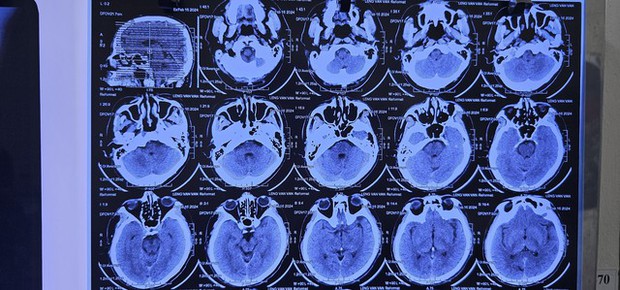

Bác sĩ nổi da gà khi nhìn ảnh X-quang của nam bệnh nhân, cảnh báo nguy cơ từ món ăn nhiều người mê - Ảnh 1.

Bác sĩ Lê Văn Thiệu, chuyên khoa Nhiễm khuẩn tổng hợp tại Bệnh viện Bệnh Nhiệt đới, vừa tiếp nhận trường hợp nam bệnh nhân đến khám với những triệu chứng đau đầu, chóng mặt, buồn nôn và đau nhức ở cơ thể. Bệnh nhân cho biết những dấu hiệu này đã xuất hiện trong khoảng 1 tuần qua.